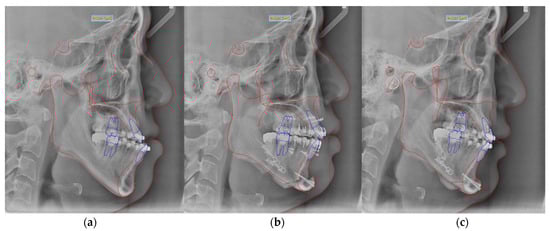

2.2. Study Methods

2.4. The Manufacturing Process of Clear Aligners by CAD/CAM